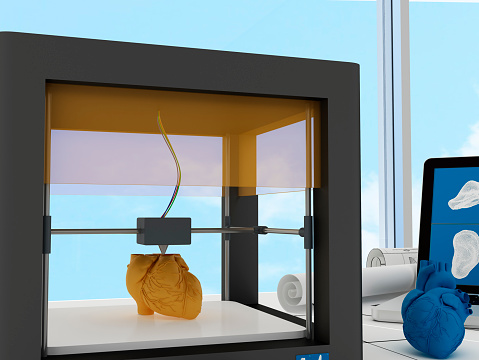

3D printing could provide treatment to osteoarthritis patients in the near future

Having something appear at the snap of our fingers is a fantasy we all have, or even simply pressing a button and making an item appear before us—think of all the uses. But alas, this is mere science fiction relegated to an episode of Star Trek. However, it is this fantasy that has lead the ...click here to read more